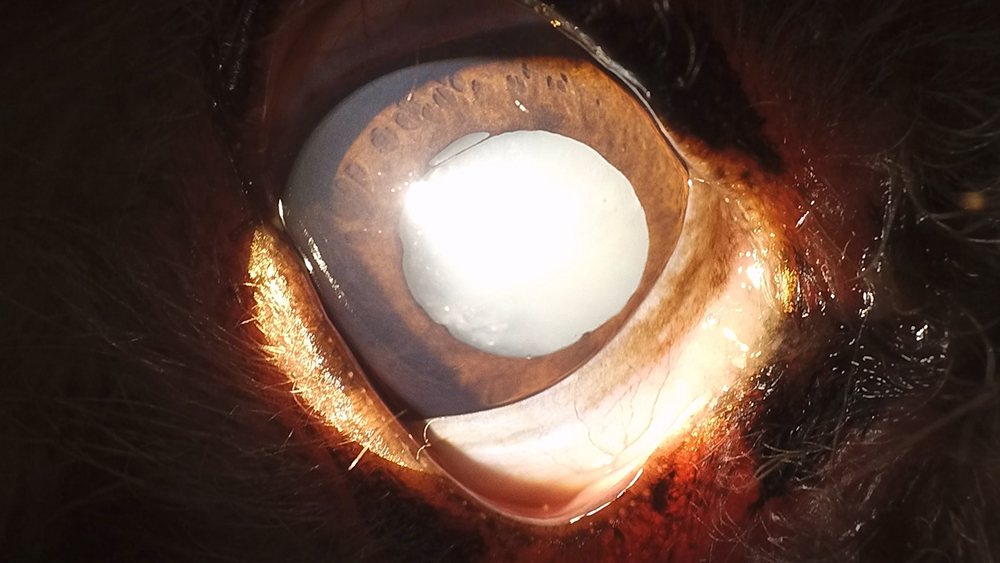

白内障

白内障は水晶体が白く濁る病気です。猫にはあまり多くありませんが、高齢の犬で比較的よく見られます。

犬の白内障は先天性のものや、糖尿病など他の疾患に伴って発症することもあります。

症状が進行すると視力が低下し、失明する可能性もあるので注意しましょう。

白内障の初期症状には、

- 物にぶつかる

- 階段の上り下りを嫌がる

- 薄暗い場所での散歩を避ける

などがあります。これらの症状が見られた際は早めにご相談ください。

白内障の治療法は大きく分けて内科療法と外科療法があります。

内科治療では点眼薬やサプリメントを用いて進行を遅らせることが可能ですが、完治は難しいです。

外科療法では、手術によって濁った水晶体を取り除きます。手術には合併症のリスクも伴いますが、視力を維持することが可能です。

白内障は早期発見と適切な治療が重要であり、当院では定期的な眼科検診をおすすめしています。